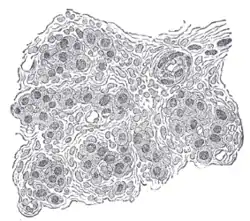

![]() Section of part of human carotid body. Highly magnified. Numerous blood vessels are seen in section among the cells. | |

The carotid body is made up of two types of cells, called glomus cells: glomus type I cells are peripheral chemoreceptors, and glomus type II cells are sustentacular supportive cells.